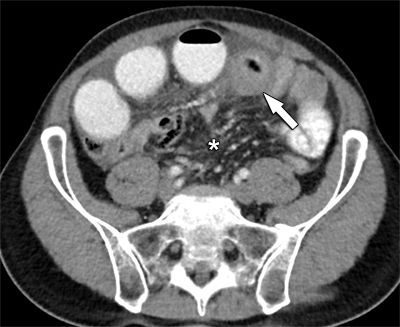

Figure 1

Axial view of contrast-enhanced CT reveals circumferential small bowel wall distention (arrow) and engorged mesenteric vessels (*).